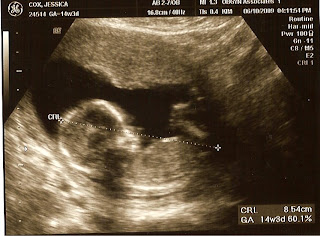

Our Precious Baby BOY:)

He was sleepy. I think he is an early morning baby.

Here are lastet pictures of our Precious Baby Boy! We didn't get the best gender shot, but Jonathan said you could really tell during the ultrasound. I was just so excited when she said BOY. I don't really remember what was going on!